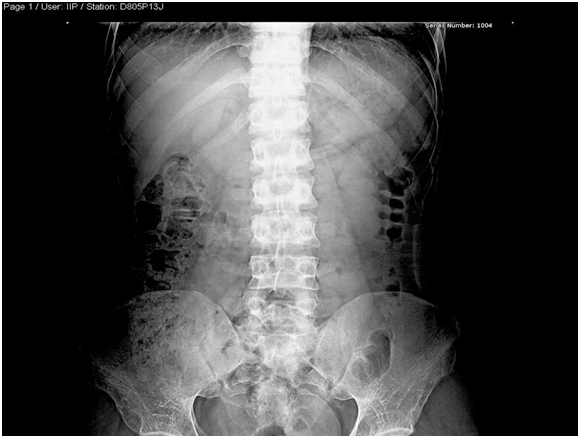

Pelvis –x-ray nov.22.2009

- R The Bones shows severe osteopenia, with appearance of Looser’s zones in the superior pubic rami, consistent with Osteomalacia…

Skeletal X-Ray: 6 months later

- Pelvis & both Femori: there is thickening of secondary bone trabeculae ,in the neck and metaphysis of both femori indicating osteopenia

- Upper Limbs & legs: normal cortical thickness but there is also thickening of secondary bone trabeculae in the distal tibia and fibula

- No Looser’s zones were detected.